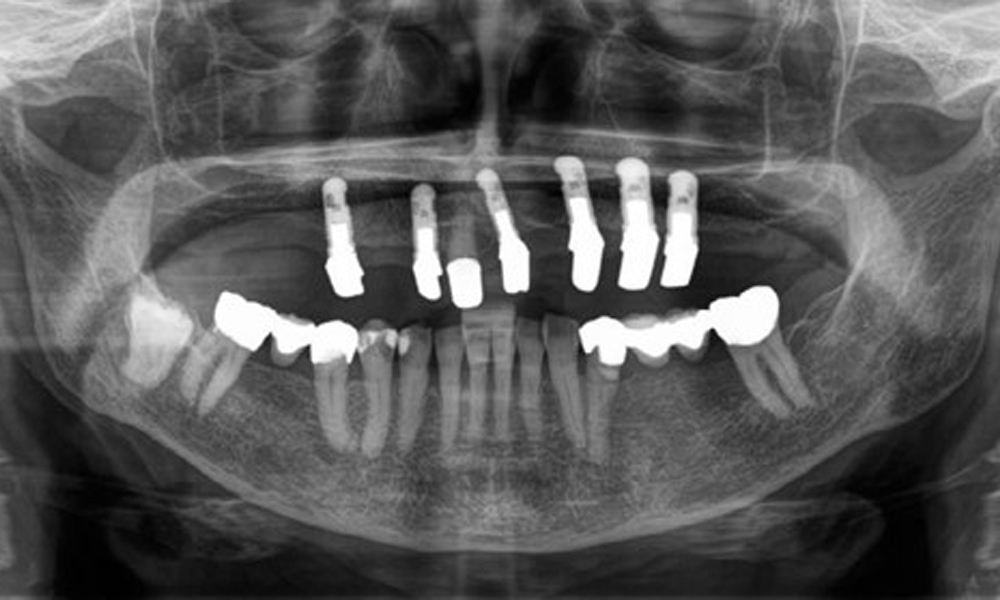

Рентгенологичните резултати показват частично беззъбо съзъбие с горночелюстни импланти за зъби 15, 13, 21, 23, 24, 25 и телескопична коронка на зъб 11. Налице са адекватни долночелюстни мостове, обхващащи участъци от 37 до 34 и от 45 до 47. Зъб 48 е засегнат. Има съмнения за вторичен кариес дистално на 43 и мезиално на 44. 44 е възстановен с нерадиационна облицовка на кухината. Налице е генерализирана хоризонтална костна загуба от приблизително 10-30 % и локализирана вертикална костна загуба, засягаща зъби 22 и 42 (фиг. 5).